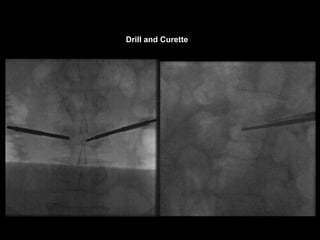

Drill and Curette

Using the Bone Curette

• in older fractures

• a specially designed curette retracted and

advanced to score the bone in the region.

• The curette is removed, and balloon

inflation is again attempted.